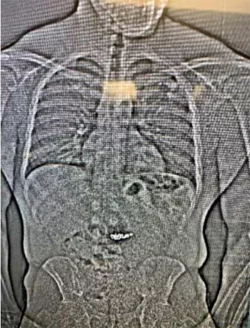

Beweisfindung per Röntgenbild: Einem Mann in Florida wird vorgeworfen, gestohlene Ohrringe im Wert von mehreren Hunderttausend Dollar verschluckt zu haben. - © Uncredited/Orlando District Attorney\\\'s office/AP/dpa

Beweisfindung per Röntgenbild: Einem Mann in Florida wird vorgeworfen, gestohlene Ohrringe im Wert von mehreren Hunderttausend Dollar verschluckt zu haben. (© Uncredited/Orlando District Attorney\\\'s office/AP/dpa)

Ermittler kamen ihm auf die Spur und nahmen ihn fest. Daraufhin soll der Mann die Ohrringe geschluckt haben. Auf einem Röntgenbild seien sie zu sehen gewesen. Der Verdächtige wurde laut US-Medien wegen Raubes und schweren Diebstahls angeklagt. Er sei bereits polizeibekannt, auch wegen eines ähnlichen Diebstahls in Texas, hieß es weiter.